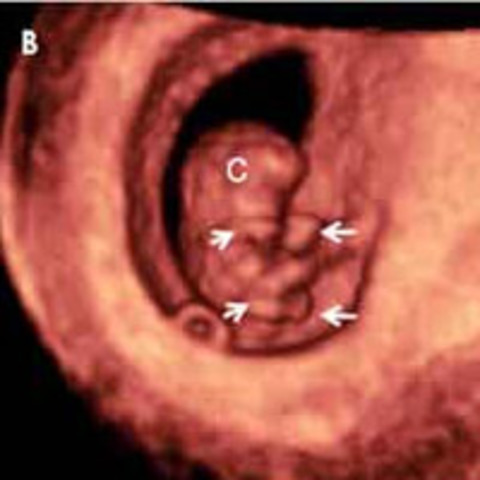

Inicio del periodo embrionario ( se prodice la formación de la mayoria de los órganos)

El embrión mide entre 2 y 4 mm, desde la cabeza hasta el final de la columna vertebral. El corazón ya esta latiendo, los ojos se estan formando, y el tubo neural se esta cerrando.

El embrión crece muy rapdio en el interior del utero materno, empieza a aparecer los vestigios de las piernas y brazos en forma de cuatro pequeños apendices. El embrión sigue teniendo una cabeza una cabeza grande en comparación con el cuerpo. Se desarrollan los intestinos y parte de las asas intestinales estan dentro del cordón umbilical en forma de hervia.